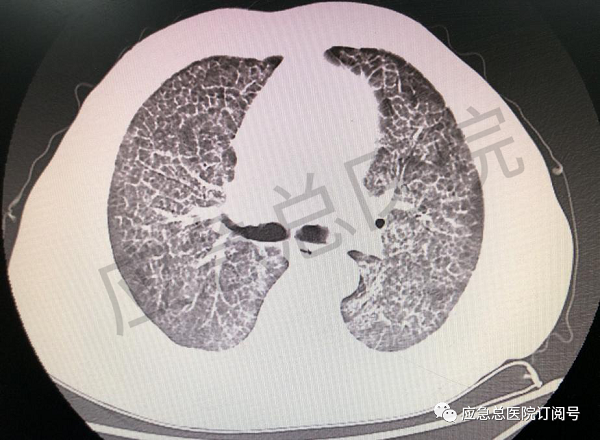

图1 肺泡蛋白沉积症患者胸部CT

肺泡蛋白沉积症(PAP),是一种罕见的肺间质性疾病,其病理特征是肺泡腔及终末细支气管内有过碘酸一希夫(PAS)染色阳性的蛋白质样沉积物;胸部高分辨CT 检查表现为弥漫性磨玻璃影、“不规则铺路石”样图案。